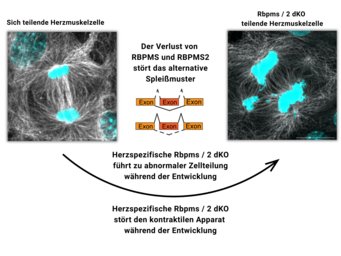

Während der Entwicklung des Embryos durchläuft das Herz kritische molekulare und strukturelle Veränderungen, die es für eine lebenslange Schwerstarbeit fit machen. Nach der Geburt stoppt die Vermehrung der Herzzellen und es werden zusätzliche Zellkerne gebildet. Gleichzeitig werden die kontraktilen Einheiten, die Sarkomere, innerhalb der Herzmuskelzellen steifer. Störungen oder Fehler in diesem Reifungsprozess sind häufig mit angeborenen Herzfehlern verbunden. Um diese zu verhindern, ist ein detailliertes Verständnis der molekularen Mechanismen, die der Reifung von Herzzellen zugrunde liegen, unerlässlich.

„Zunächst haben wir Mäuse untersucht, denen genetisch nur einer der beiden Spleißfaktoren der RBPMS/RBPMS2-Familie fehlt. Bemerkenswerterweise zeigten die Mäuse trotz der Inaktivierung von RBPMS eine normale Herzentwicklung und normale Herzfunktion nach der Geburt“, sagt Shan Lin, Erstautor der Studie. Als Nächstes inaktivierte Shan auch RBPMS zusammen mit RBPMS2, was zu schweren Defekten bei der Herzentwicklung und dessen Funktion führte. „Die gleichzeitige Inaktivierung von RBPMS und RBPMS2 hat uns gezeigt, dass der Verlust eines Gens während der Herzentwicklung durch andere Gene kompensiert werden kann“, erklärt Lin.

Aber welche molekularen Prozesse werden durch Spleißproteine gesteuert? „Unsere Studien haben gezeigt, dass RBPMS und RBPMS2 eine Schlüsselrolle bei mehreren grundlegenden Prozessen der Herzentwicklung spielen”, so Lin. Die Gruppe entdeckte, dass RBPMS und RBPMS2 nicht nur die Bildung von Isoformen für Proteine des Sarkomers steuern, sondern auch die Bildung des Spindelapparats regulieren, der für die Zellteilung unerlässlich ist. „Wenn beide Proteine inaktiv sind, ist die Zellteilung gestört“, erklärt Lin.